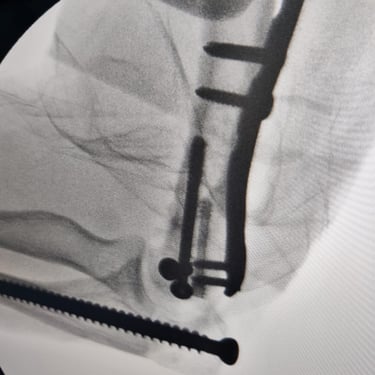

Limb reconstruction and complex trauma surgery

Trauma (Fractures)

Orthopedic trauma (fractures) refers to injuries to the musculoskeletal system, like bones, joints, and muscles, often from accidents, falls, or sports